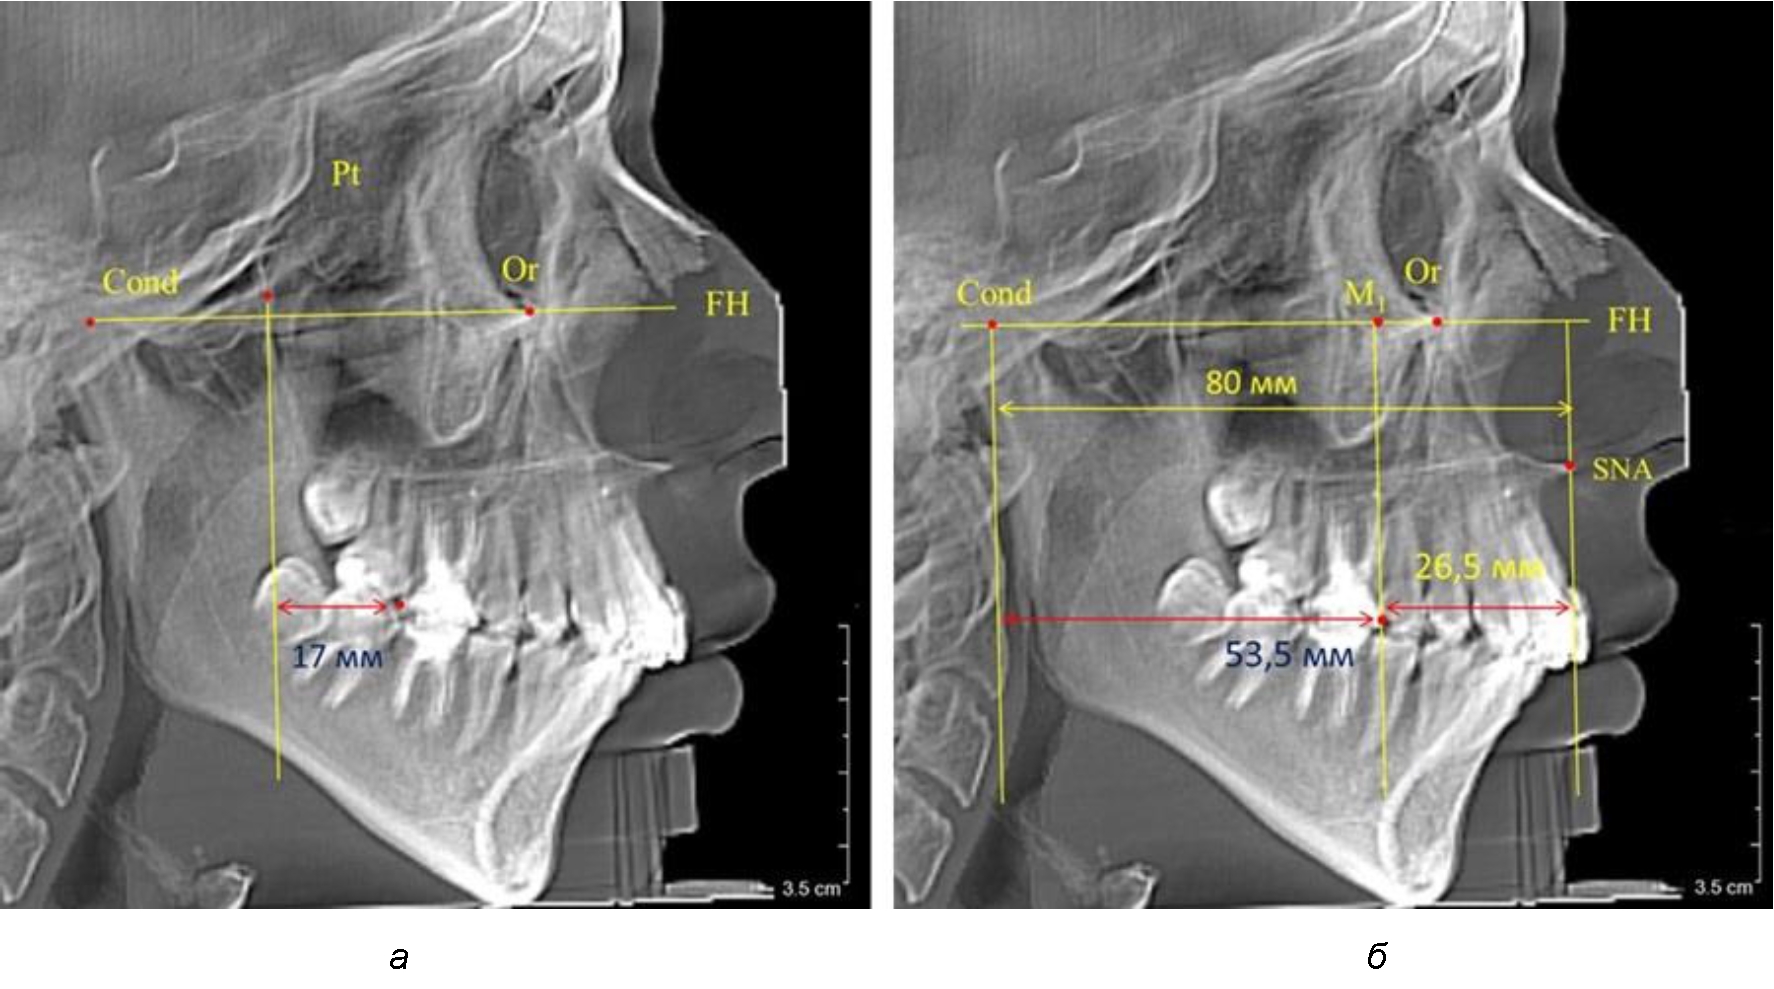

Рис. 3. Особенности положения первых моляров по R. E. McDonald (а) и по предложенному методу (б) при увеличенном молярно-крыловидном расстоянии

В то же время при увеличенном расстоянии от крыловидной вертикальной плоскости PTV до дистальной поверхности верхнего первого постоянного моляра, равное 23 мм, сагиттальный размер гнатического отдела составил 92 мм. При этом отношение кондилярно-спинального расстояния к кондилярно-молярному размеру (30,5), так же, как и при малых размерах, было близким к коэффициенту 1,5, что представлено на рис. 3.

Таким образом, наблюдалась эффективность использования относительных показателей при определении положения первых постоянных моляров. При этом наиболее целесообразно и с методологической точки зрения верным, было использование медиальной поверхности первого постоянного моляра. Построенная таким образом молярная линия отграничивала отдел зубной дуги с замещающими зубами от дистального отдела с добавочными зубами постоянного прикуса, в частности, постоянных моляров.

Второй частью исследования был анализ положения первых постоянных моляров в различные периоды сменного прикуса. На телерентгенограммах детей периода прикуса молочных зубов дистальная поверхность зачатка первого постоянного моляра отстояла от крыловидной вертикали на величину, составляющую около 7 мм, что было близким по значению к данным R. E. McDonald. Сагиттальный размер гантического отдела составлял около 60 мм, а его отношение к кондилярно-молярной глубине – 1,5 (рис. 4).